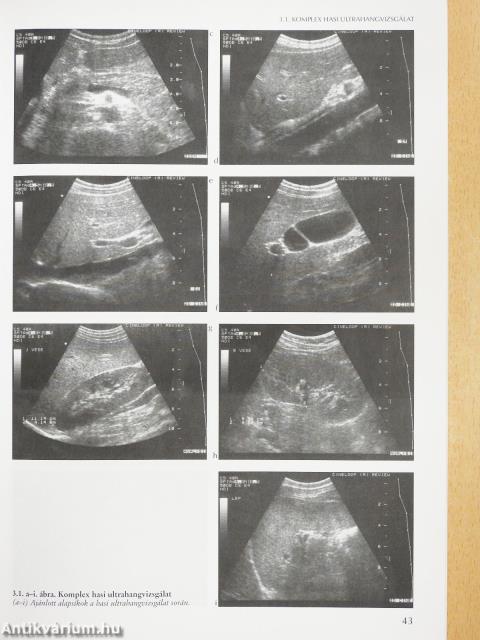

Komplex hasi ultrahangvizsgálat42